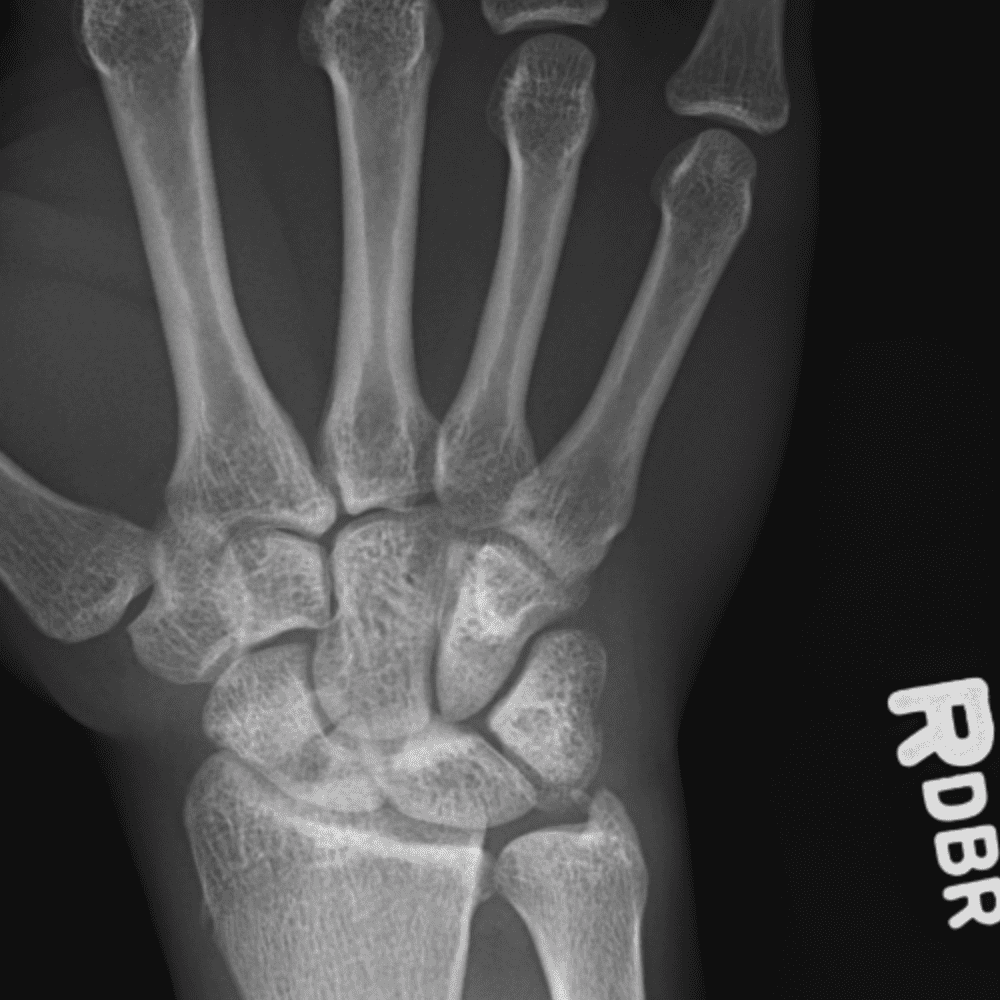

Simuliert den Dienst durch subtile oder schwierige Fälle und einige Normalbefunde.

30 Fälle